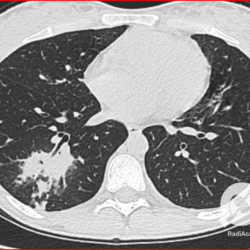

Os agentes etiológicos infecciosos são variados (bactérias, vírus, fungos, parasitas…), mas o que ocorre nos pulmões durante uma infecção por qualquer tipo de agente é a substituição do ar alveolar por secreção (pus, muco, eventualmente sangue ou necrose…) e com isso a manifestação radiográfica vai ser a mesma já que todas estas secreções apresentam a mesma densidade radiográfica: partes moles.

E o nome dado a esta alteração radiográfica que corresponde à substituição do ar alveolar por líquido é a consolidação alveolar.

Uma consolidação alveolar é, por definição, uma opacidade (imagem densa, branquinha) homogênea ou às vezes heterogênea (pela presença de calcificações ou cavidades), de limites mal definidos, exceto quando toca a pleura da parede ou das cissuras pulmonares. É um termo usado tanto em radiografia, como em tomografia computadorizada. Na tomografia, um outro termo é usado: vidro fosco, que é uma opacidade (branquinha mas não tanto como a consolidação), que borra o pulmão mas deixa ver os vasos de permeio (igual bigode de adolescente: dá pra ver todo o fundo).

Nós vamos mostrar aqui um pequeno apanhado de pneumonias de variados agentes, em diversos segmentos e lobos pulmonares, com extensões variadas. O objetivo é identificar o padrão radiológico de consolidação alveolar e não determinar o agente infeccioso, isso vai ser assunto para mais adiante. Aliás já antecipo que é fundamental saber localizar a lesão, porque alguns destes bichos gostam de determinados segmentos, alguns tumores também têm as suas preferências, então localização é fundamental. Se localização não fosse importante, um apartamento na beira do mar sairia o mesmo preço de um apartamento de frente pra BR-101, concordam?